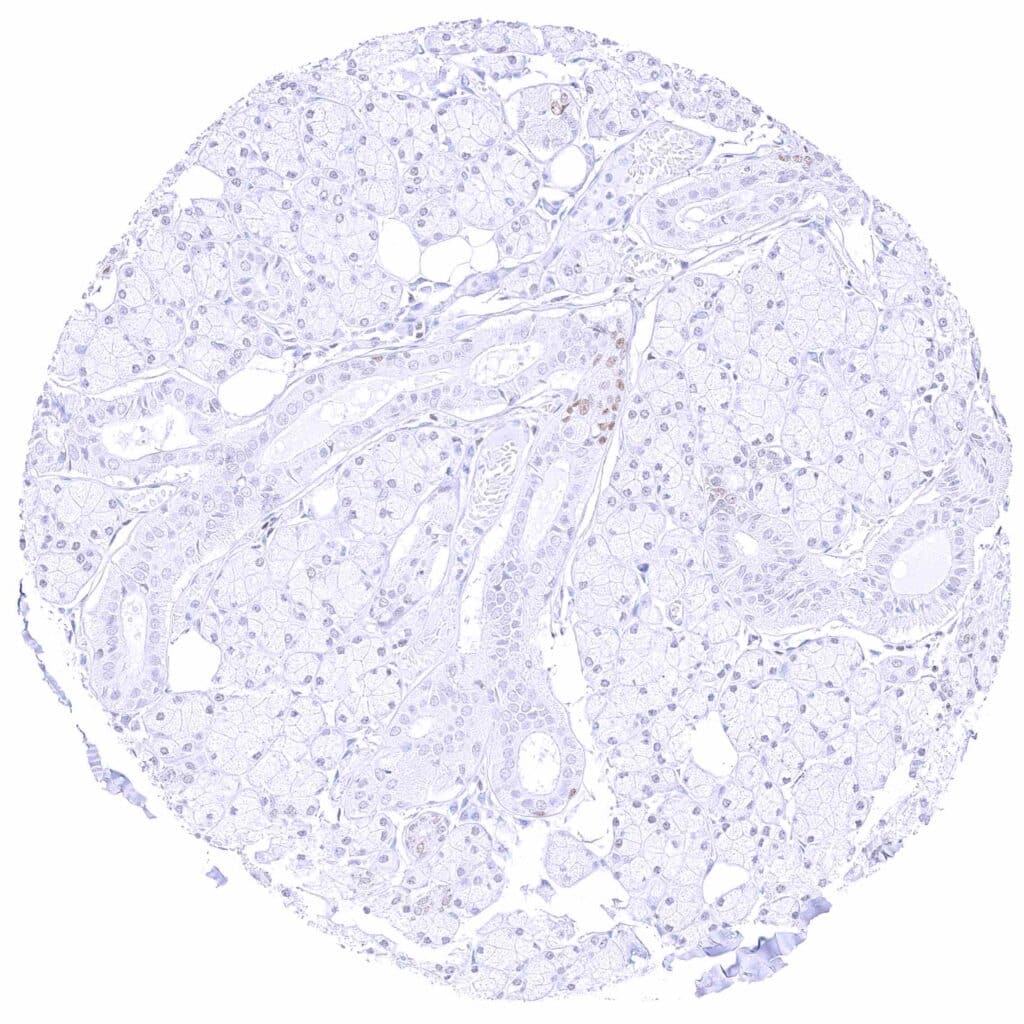

Kidney, cortex – Moderate to strong, nuclear GATA3 positivity of collecting ducts, some cells of distal tubuli, and of podocytes.

Kidney, medulla – Moderate to strong, nuclear GATA3 positivity of some collecting ducts.

Kidney, pelvis, urothelium – Strong nuclear GATA3 positivity of all urothelial cells.